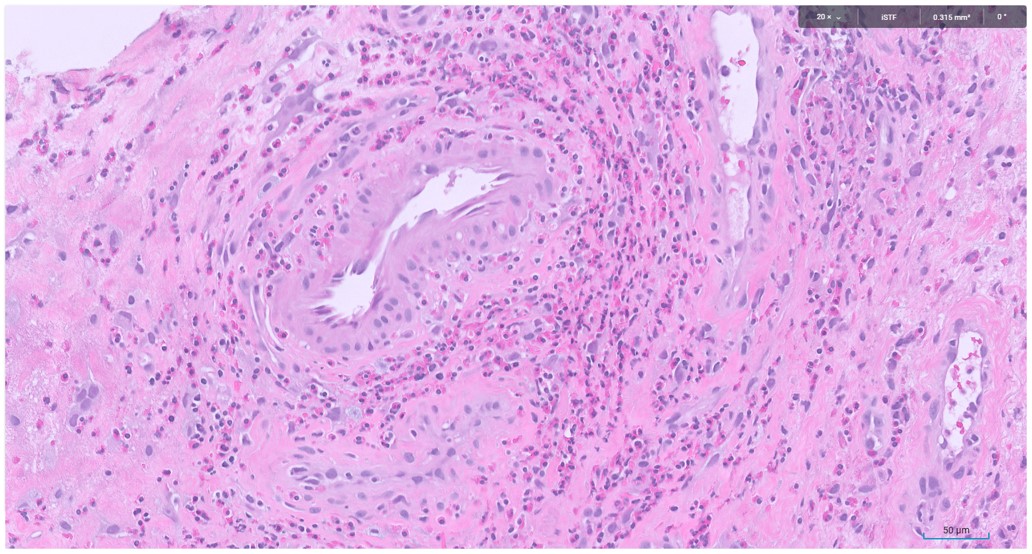

Microscopic image possibly detecting cancerous areas in human tissue

What is the most likely diagnosis?

1. Radiation cystitis

2. Cystitis cystica

3. Invasive urothelial carcinoma

4. carcinoma in situ

Radiation cystitis